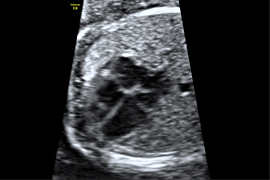

Frühe Organdarstellung

12. Schwangerschaftswoche

Schon gegen Ende des ersten Schwangerschaftsdrittels sind alle kindlichen Organe angelegt. Auch wenn Sie keine Untersuchung zur Vorhersage des Risikos für eine genetische Veränderung (I. Trimesterscreening s.o.) wünschen, ist eine frühe Darstellung der Organe des Embryos sinnvoll, da hier schon viele schwere Entwicklungsstörungen ausgeschlossen werden können.

Zum jetzigen Zeitpunkt können bereits Gehirn, Herz, Zwerchfell, Magen, Bauchwand und Harntrakt sowie die Kopfkontur und die Extremitäten dargestellt werden. Einen „großen Ultraschall“ im 2. Drittel der Schwangerschaft kann diese Untersuchung allerdings noch nicht ersetzen.

In der 20. Schwangerschaftswoche ist das kindliche Herz etwa so groß wie eine Himbeere – und trotzdem können wir bereits die Kammern und Herzklappen und die zu- und abführenden Blutgefäße darstellen!

Herz 4 Kammern

Durch eine sehr spezielle Ultraschalluntersuchung können die kindlichen Organe eingehend untersucht werden. Hierbei wird ihre Struktur dargestellt und die Funktion (z.B. des kindlichen Herzens) überprüft. Eine Vielzahl von leichten und schweren Entwicklungsstörungen können hierbei ausgeschlossen werden.

Bei der fetalen Echokardiographie (Herz-Ultraschall) wird das Herz bis ins Detail dargestellt und untersucht (Wände, Kammern, Klappen, Blutgefäße und die Beweglichkeit des Herzens); hierfür wird zusätzlich die farbkodierte Dopplersonographie angewandt, welche die Blutflussrichtung sichtbar macht.